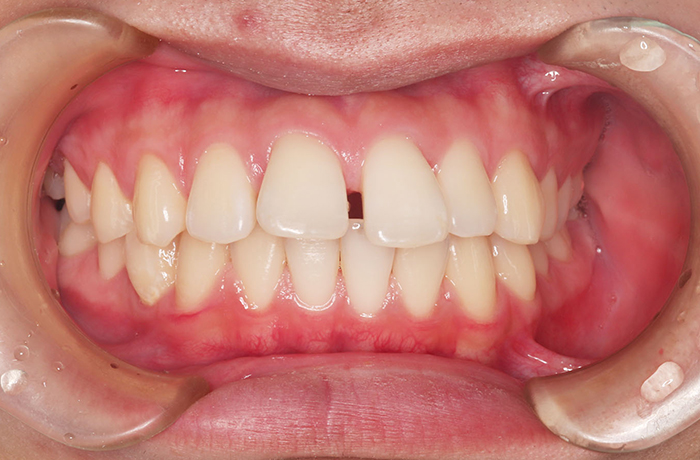

M様

治療前

年齢 21歳

性別 男性

治療名称 マウスピース型カスタムメイド矯正歯科装置(インビザライン)・コンプリヘンシブパッケージ(フルパッケージ)

総額治療費用 770,000円(税込10%) 金額備考 精密検査料・診断料 33,000円(税込10%)

治療期間 1年 通院頻度など 1か月ごと

その他治療に関する情報

治療内容

患者の症状 上顎前突、前歯離開

治療方法 マウスピース型カスタムメイド矯正歯科装置(インビザライン)による矯正

治療結果 歯列改善、咬合状態が良くなりました。

※治療結果は患者様によって個人差があります。

治療を行う上での注意点

リスク/副作用 20時間以上、装置の装着時間が必要です。